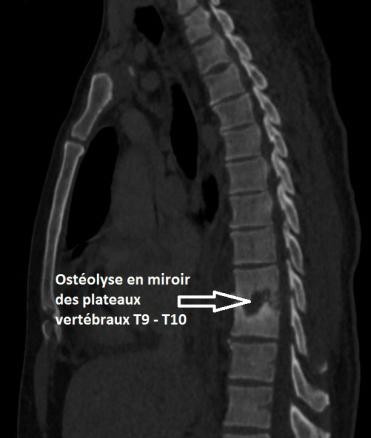

Ostéolyse vertébrale évocatrice de spondylodiscite évolutive

Scanner thoracique, coupe sagittale, fenêtre osseuse.